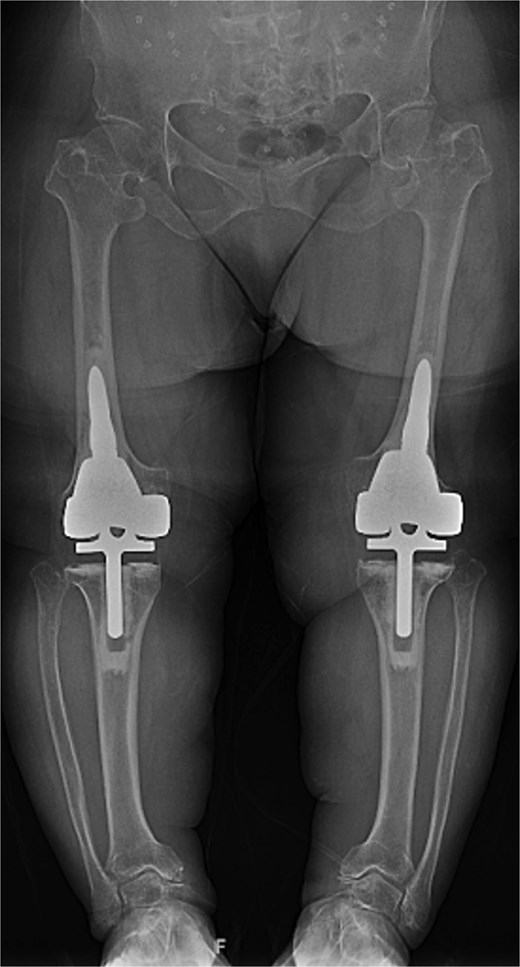

A 61-year-old woman with a history of achondroplasia, gastroesophageal reflux disease, depression, and sciatica presented with progressively worsening bilateral knee pain, mechanical symptoms, and significant difficulty with ambulation. The patient had a body mass index (BMI) of 41.1 kg/m2 and a characteristic short-limb SD phenotype consistent with achondroplasia. On physical examination, the patient demonstrated bilateral varus alignment of the lower extremities and gait assessment revealed a significant varus thrust and valgus instability in mid-stance. Bone length radiographs revealed severe medial joint space narrowing, metaphyseal flaring of the tibia and femur, and bilateral mechanical axis varus deformity measuring 36 and 44 degrees on the left and right legs, respectively (Fig. 1).

Preoperative standing AP radiographs demonstrating severe bilateral mechanical axis varus deformity measuring 36 and 44 degrees on the left and right legs, respectively.